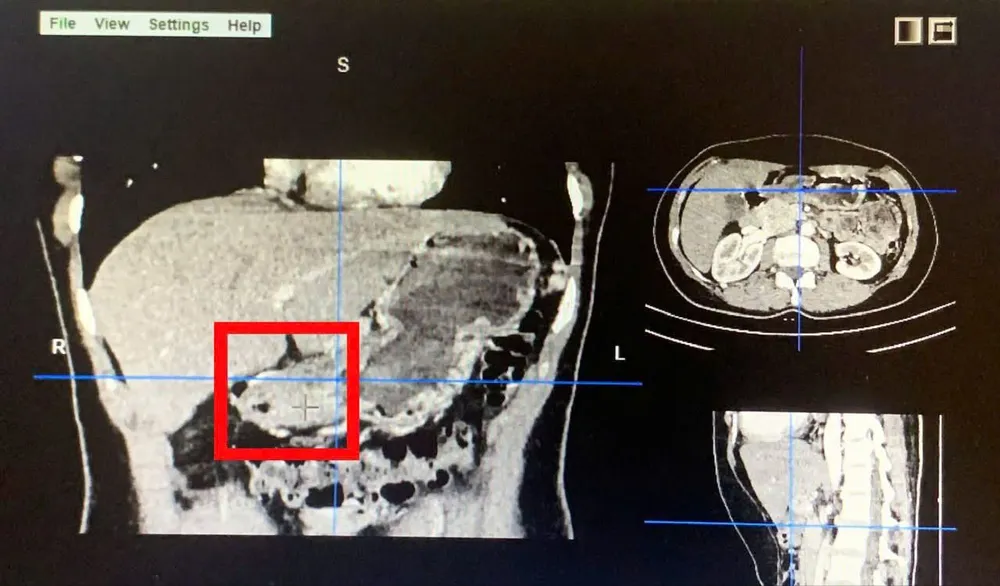

Khối u trên phim CT bụng. Ảnh: BVCC

Qua nội soi dạ dày, các bác sĩ phát hiện tổn thương ổ loét lớn bờ sượng cứng vùng bờ cong nhỏ - hang vị dạ dày. Kết quả sinh thiết cho thấy đây là trường hợp Carcinoma tuyến kém biệt hoá tại dạ dày.

Ngày 3-4, hơn 2,5 giờ đồng hồ bệnh nhân được phẫu thuật nội soi cắt gần toàn bộ dạ dày và nạo vét hạch tiêu chuẩn.